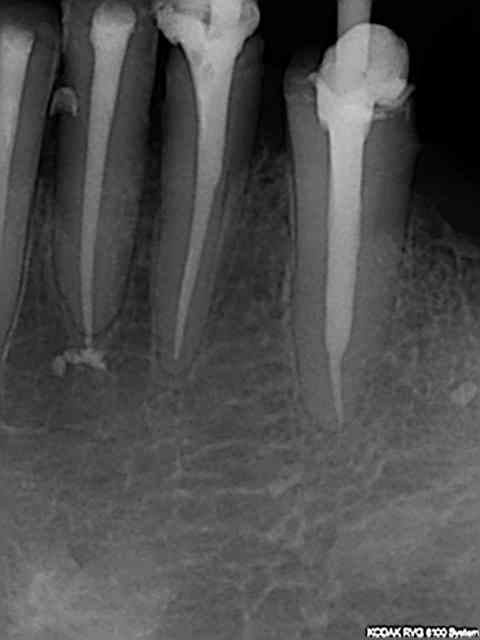

J'ai fait une reprise de TR sur 27 en novembre dernier ; digue, javel, NiTi, pour un bon résultat radio.

Si-si il a raison les radios exposées en nombre font toutes preuve d'un traitement parfait et ce en un temps plus que raisonnable.

Radio cone 25 en place etc....)))) j'avoue je pèche dans le etc !)))

"Le" gros plus ces derniers mois a été l'apparition du r25 réciproc qui a permis de supprimer les s2,f1, f2 protaper et ce sans casse ni fausse route à ce jour ! une révolution en rupture de stock en ce moment.))))